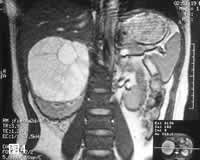

MRI:病灶T2WI呈高信号强度,多房状结构清楚,间隔为低信号,右肾静脉及下腔静脉内未见瘤栓征象(图3)。冠状层面显示肿瘤与残余肾下极间分界清楚,外缘光滑(图4)。